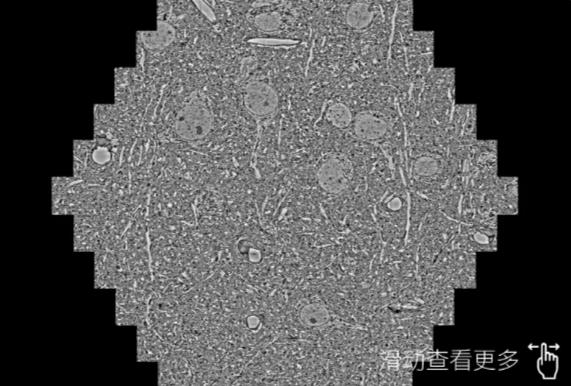

鼠脑切片。左图使用白山蔡司白山扫描电镜MultiSEM706对165μmx143pm面积区域成像,耗时仅需1.5秒。右图为鼠脑切片中30μm区域放大效果。样品由芝加哥大学B.Kasthuri提供。

使用蔡司高速白山扫描电镜MultiSEM对1mm²人脑皮层组织进行高分辨成像,并对其中的各种细胞结构进行三维重构分析。左图展示了2x3mm²组织平面中锥体神经元的三维重构效果。右图显示了局部体积神经元三维重构。图像由哈佛大学chtman实验室提供,渲染图由D. Berger 制作。